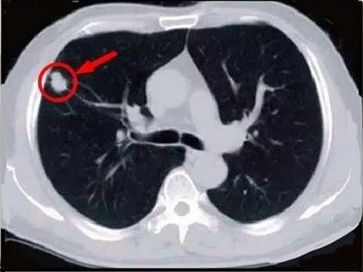

肺結節(jié)

什么是肺結節(jié)?

肺結節(jié)是指胸部CT 檢查影像圖片所見,肺內有直徑≤3cm的圓形、類圓形或不規(guī)則形密度增高陰影,可單發(fā)或多發(fā),邊界清晰或不清晰的病灶。

那么,什么樣的肺結節(jié)惡性的風險大呢?

統(tǒng)計表明,在檢出的肺部小結節(jié)中,惡性僅占5%左右。初次肺CT檢查發(fā)現(xiàn)的肺部小結節(jié)中,90%左右都是良性病變,但在直徑大于25mm的肺內單發(fā)結節(jié)中,惡性的占到一半以上。

我們從以下幾個方面來初步判斷肺結節(jié)惡性的風險:

1.看大?。?/strong>在多個肺癌篩查試驗中發(fā)現(xiàn),直徑大于20毫米的肺結節(jié),惡性概率為64%~82%;直徑11~20毫米的肺結節(jié),惡性概率為33%~64%;直徑6~10毫米的肺結節(jié),惡性概率為6%~28%;直徑小于5毫米的肺結節(jié),惡性概率在1%以內。

指南上通常以8毫米為界,大于8毫米的結節(jié)一定要去醫(yī)院找專業(yè)的胸外科、呼吸科醫(yī)生評估,盡早診治。

3.看結節(jié)特征:肺磨玻璃結節(jié)為例,通常直徑越大,其惡性可能性越大,邊緣光滑、界線清晰者良性可能性大;而邊界不規(guī)則、邊緣毛刺征、分葉征多是惡性病灶的重要征象。